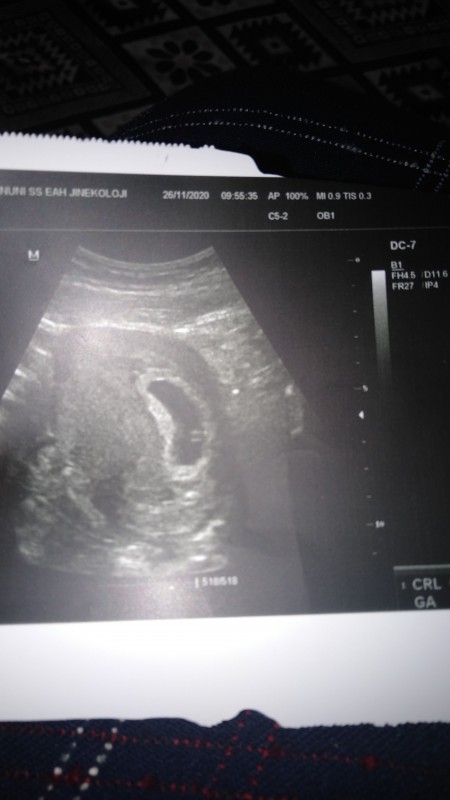

Kizlar bugün kontrolum vardı çok şükür kalp atışlarını dinledim  fakat doktorum kesen büyük dedi o ne oluyo geri kalan hersey normal

1. imagebide ben 7 haftakik diye hesaplarken doktorum 6+3. Dedi

Gebelik haftası 6+3